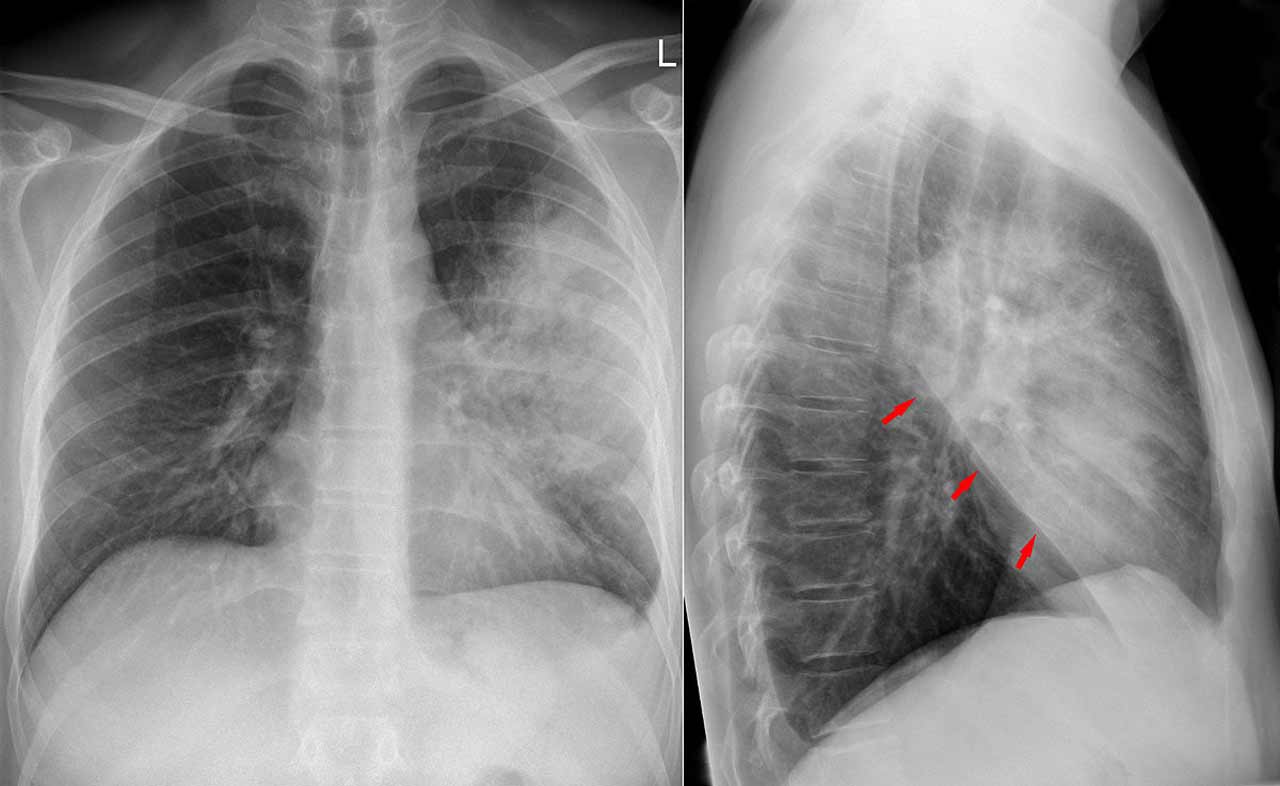

I medici hanno poi trapiantato i polmoni in una donna affetta da una malattia polmonare cronica all’ospedale universitario di Ann Arbor. Il dottor Daniel Richard Kaul, direttore del Transplant Infectious Disease Service del Michigan Medical School, si è difeso dicendo che i campioni di naso e gola raccolti da donatori e riceventi di organi all’inizio sono risultati negativi al Covid. E ha aggiunto: «Non avremmo assolutamente usato i polmoni se avessimo avuto un test Covid positivo. Tutti controlli che normalmente facciamo e siamo in grado di fare, li abbiamo fatti». Secondo lo studio, però, il terzo giorno dopo il trapianto la donna «ha sviluppato un peggioramento», che ha portato a un’infezione polmonare. Dopo lo shock settico i medici hanno eseguito sulla paziente il test del Coronavirus, risultato positivo.

«L’anamnesi ottenuta dalla famiglia non ha rivelato precedenti di febbre, tosse, mal di testa o diarrea recenti», si legge nello studio. «Non è noto se il donatore abbia avuto esposizioni recenti a persone note o sospettate di essere infette da Sars-CoV-2». Dall’analisi di un campione di fluido prelevato dai polmoni donati prima di essere impiantati è infine emersa la positività al Covid-19. I ricercatori affermano che «sia il ricevente del trapianto sia il chirurgo hanno contratto il Sars-CoV-2 dai polmoni del donatore».